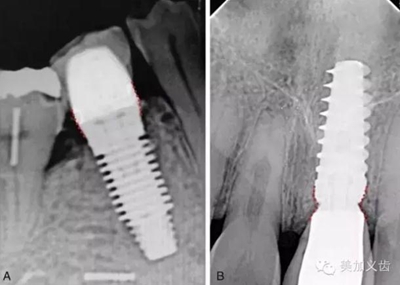

根尖片屬于最最基本的口腔二維影像學(xué)檢查,很難看到重要的解剖部位,除非采用嚴(yán)格的平行投照技術(shù),否則拍攝角度的變化對測量數(shù)值的準(zhǔn)確性有很大的影響。

其優(yōu)點是:分辨率高,能看到局部細(xì)節(jié),費用比較低,患者都能夠接受,而且操作也比較簡單,醫(yī)生和護士都能很快學(xué)會,放射劑量相對很小,對醫(yī)生和患者的影響都不大,國外已經(jīng)普遍在診室拍攝根尖片了,國內(nèi)還沒有得到允許。

其缺點是:看到的范圍實在是太小了,無法用來評估術(shù)區(qū)骨量的多少,而且因為拍攝角度的問題,尤其是上后牙,你肯定見過某些上6的顎根已經(jīng)長到上頜竇里了,其實并沒有,只是拍攝角度所導(dǎo)致。如果僅僅通過根尖片檢查就開展種植,其風(fēng)險可想而知,可以說是對患者和自己都不負(fù)責(zé)任的做法。

但根尖片是種植中必不可少的檢查,可以用來檢查基臺與種植體、修復(fù)體與基臺之間的密合程度,或者用于術(shù)后隨訪。

值得注意的是:使用根尖片來進行術(shù)后隨訪,這是種植術(shù)后很重要的一件事情,而且需要定期來做,然后將拍攝出來的根尖片進行對比,才能看到是否有骨吸收。但如果你每次拍攝的角度都不一樣,結(jié)果會讓你嚇一跳,怎么某段時間內(nèi)骨吸收這么多?!怎么某段時間骨頭又長上來了?!太令人費解了!

3.jpg

其實是你拍攝的角度不一樣,所得到的結(jié)果也不一樣,因此,采用平行透照技術(shù)就十分關(guān)鍵,否則你的術(shù)后回訪是沒有意義的。平行透照技術(shù)很簡單,通過X線片定位器就可以做到,讓你的X線接收器和管球平行,這樣每次拍攝的角度都是一樣的了。